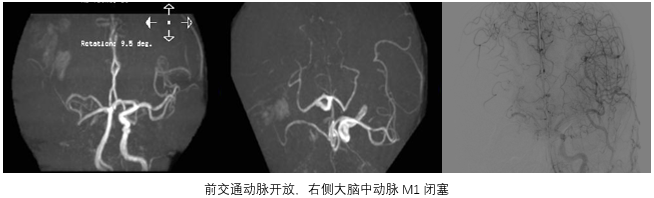

结论:左侧大脑半球多发梗死灶,T2 flair高信号区域小,左侧颈内-大脑中闭塞,T1 flair提示小出血灶后通过CT排除出血,初步确认为梗死/坏死。

• 首先放置1型弓,排除左侧颈源系统嫌疑,右侧颈源系统由右向左通过软脑膜部分代偿,后循环向前循环少许代偿。

• 左颈总造影显示C1远端逆流,提示串联病变。

• 输送微导丝与中间管,中间管抽吸后在C7段冒烟(A),遂进行微导管造影(B)

• 将中间管送至AB段进行抽吸,中间管只能在M1中段抽吸。

• 抽吸后正位造影显示颅内操作效果良好。

• 输送保护伞,保护伞下撤指引造影侧位C1狭窄。

• 4*30球囊预扩后,将7*40 Carotid Wallstent支架植入后正位,血流得到明显恢复。

• 术后即刻:去碘CT排除出血风险,梗死灶出现。

• 术后一天:DWI显示梗塞面积没有明显增大,MRA提示血管再通,发现存在LMCA动脉瘤。

• 术后四天:CT显示没有出血表现,梗死灶已经形成。

• 术后3个月:复查CT显示恢复情况良好。